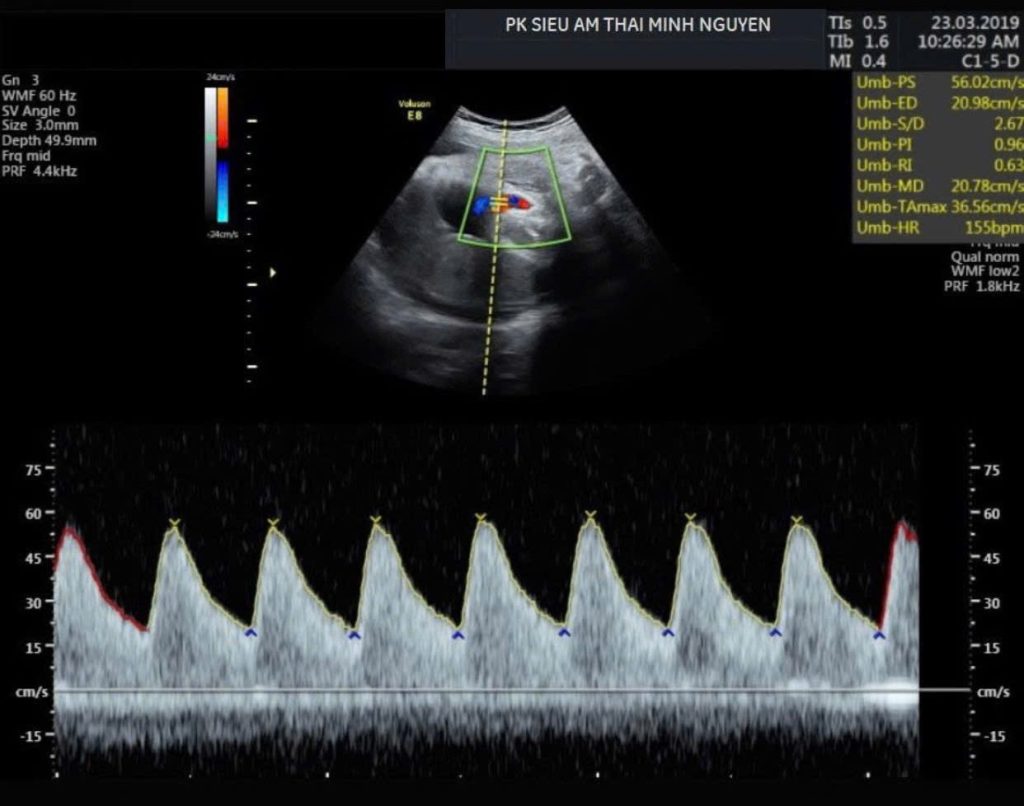

Sau khi siêu âm lại đầy đủ sinh trắc chuẩn và làm doppler động mạch rốn, động mạch não giữa, kết quả cho thấy thai dưới bách phân vị thứ 8 nhưng dòng máu nuôi thai còn trong giới hạn bình thường. Nên kế hoạch theo dõi sát mỗi 10 ngày được đưa ra thay vì chấm dứt thai kỳ sớm.

Đánh giá doppler động mạch rốn

Doppler động mạch rốn phản ánh sức cản mạch máu bánh nhau. Khi bánh nhau hoạt động kém, chỉ số trở kháng tăng. Dòng chảy cuối tâm trương có thể giảm hoặc mất.

Trường hợp nặng có thể xuất hiện đảo ngược dòng chảy cuối tâm trương. Đây là dấu hiệu quan trọng để đẩy cao giá trị siêu âm thai chậm tăng trưởng

Không chỉ nhìn cân nặng mà phải đánh giá dòng máu nuôi thai và diễn tiến theo thời gian. Nếu doppler động mạch rốn bình thường, có thể tiếp tục theo dõi sát. Còn nếu trường hợp doppler xấu dần, cần cân nhắc thời điểm chấm dứt thai kỳ.